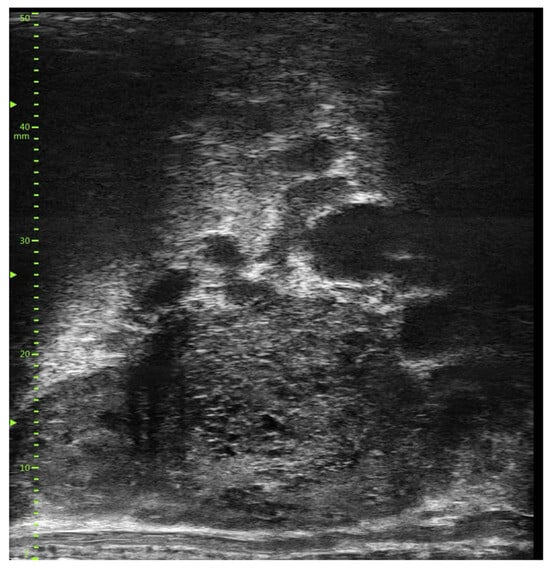

- Ghai, S.; Eure, G.; Fradet, V.; Hyndman, M.E.; McGrath, T.; Wodlinger, B.; Pavlovich, C.P. Assessing Cancer Risk on Novel 29 MHz Micro-Ultrasound Images of the Prostate: Creation of the Micro-Ultrasound Protocol for Prostate Risk Identification. J. Urol. 2016, 196, 562–569. [Google Scholar] [CrossRef]

- Abouassaly, R.; Klein, E.A.; El-Shefai, A.; Stephenson, A. Impact of using 29 MHz high-resolution micro-ultrasound in real-time targeting of transrectal prostate biopsies: Initial experience. World J. Urol. 2020, 38, 1201–1206. [Google Scholar] [CrossRef]

- Klotz, L.; Lughezzani, G.; Maffei, D.; Sanchez, A.; Pereira, J.G.; Staerman, F.; Cash, H.; Luger, F.; Lopez, L.; Sanchez-Salas, R.; et al. Comparison of micro-ultrasound and multiparametric magnetic resonance imaging for prostate cancer: A multicenter, prospective analysis. Can. Urol. Assoc. J. 2020, 15, E11–E16. [Google Scholar] [CrossRef]

- Pedraza, A.M.; Gupta, R.; Musheyev, D.; Pino, T.; Shah, A.; Brody, R.; Wagaskar, V.; Kaufmann, B.; Gorin, M.A.; Menon, M.; et al. Microultrasound in the detection of the index lesion in prostate cancer. Prostate 2024, 84, 79–86. [Google Scholar] [CrossRef]

- Ditonno, F.; Franco, A.; Manfredi, C.; Veccia, A.; Valerio, M.; Bukavina, L.; Zukowski, L.B.; Vourganti, S.; Stenzl, A.; Andriole, G.L.; et al. Novel non-MRI imaging techniques for primary diagnosis of prostate cancer: Micro-ultrasound, contrast-enhanced ultrasound, elastography, multiparametric ultrasound, and PSMA PET/CT. Prostate Cancer Prostatic Dis. 2023, 27, 29–36. [Google Scholar] [CrossRef]